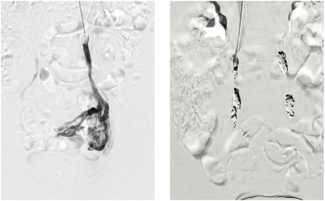

The author presents a case in which the Artix Thrombectomy System (Inari Medical) was utilized in a hybrid procedure to revascularize a thrombosed axillary-profunda bypass graft followed by profundoplasty.